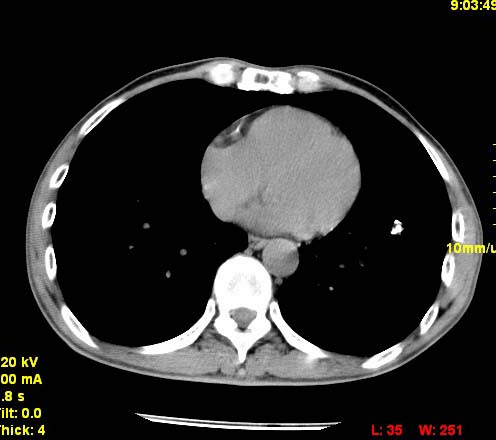

以下是引用wangzhengyuan在2007-11-11 23:31:00的发言:[br]钙化灶,看上去不像转移。

以下是引用zjzjr在2007-11-12 8:35:00的发言:[br]考虑错构瘤,建议定期复查.

以下是引用卜一在2007-11-12 5:59:00的发言:[br]病灶本身不像转移,不知有没有以前的胸部ct片,若有,则可以对比以下,若是新出现病灶,应高度警惕“转移”的可能![br]